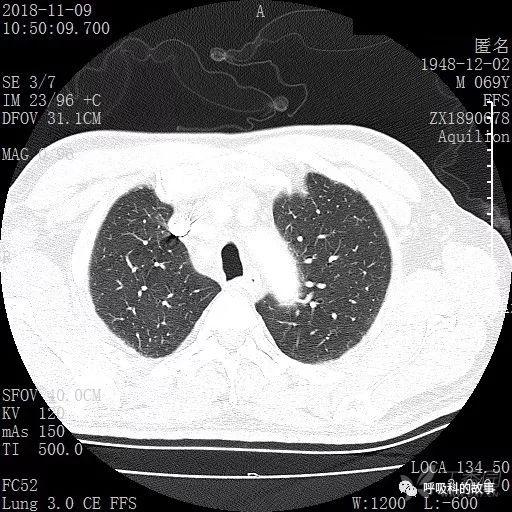

胸部增强CT示右肺门占位伴远端阻塞性肺炎,纵膈、右肺门、右侧颈根部、右侧腋下及肝门部肿大淋巴结。两侧胸腔少量积液。

肺窗CT